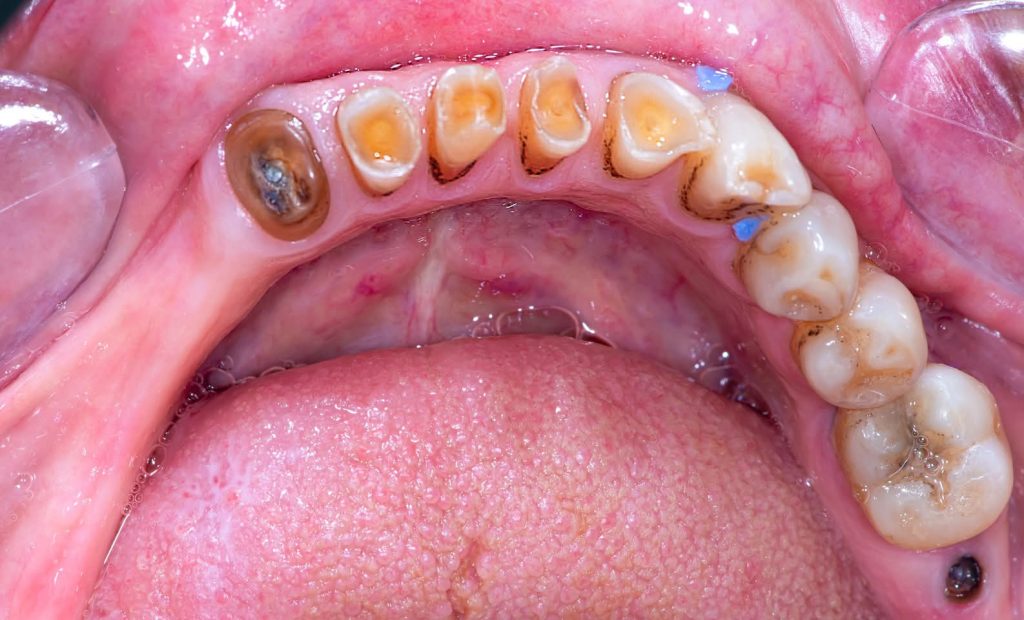

2. Corrective Phase:

This phase included all necessary corrective procedures:

Extraction of hopeless teeth.

Endodontic treatments.

Replacement of old, defective fillings.

Tooth build-ups to the new vertical dimension of occlusion, aided by the silicone indices.